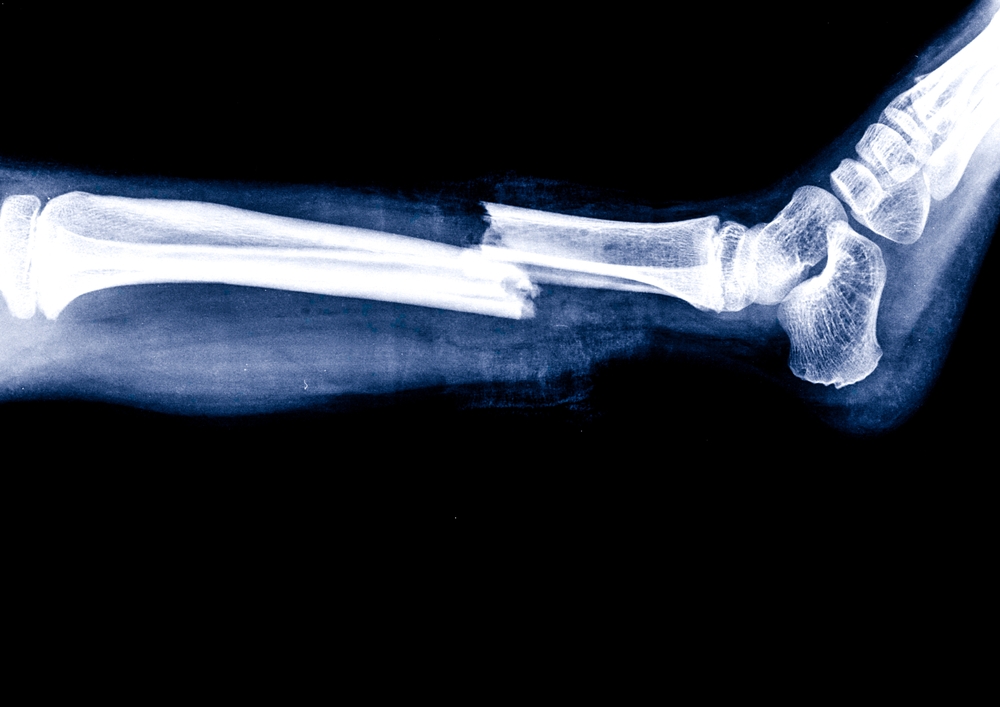

An X-ray can help distinguish between a sprain, which affects ligaments, and a fracture, which involves the bone. This distinction is important because treatment plans can differ significantly depending on the diagnosis.

X-rays are widely used to identify fractures, dislocations, and alignment issues within the bones and joints. They can also help rule out more serious structural concerns when symptoms are mild but persistent.